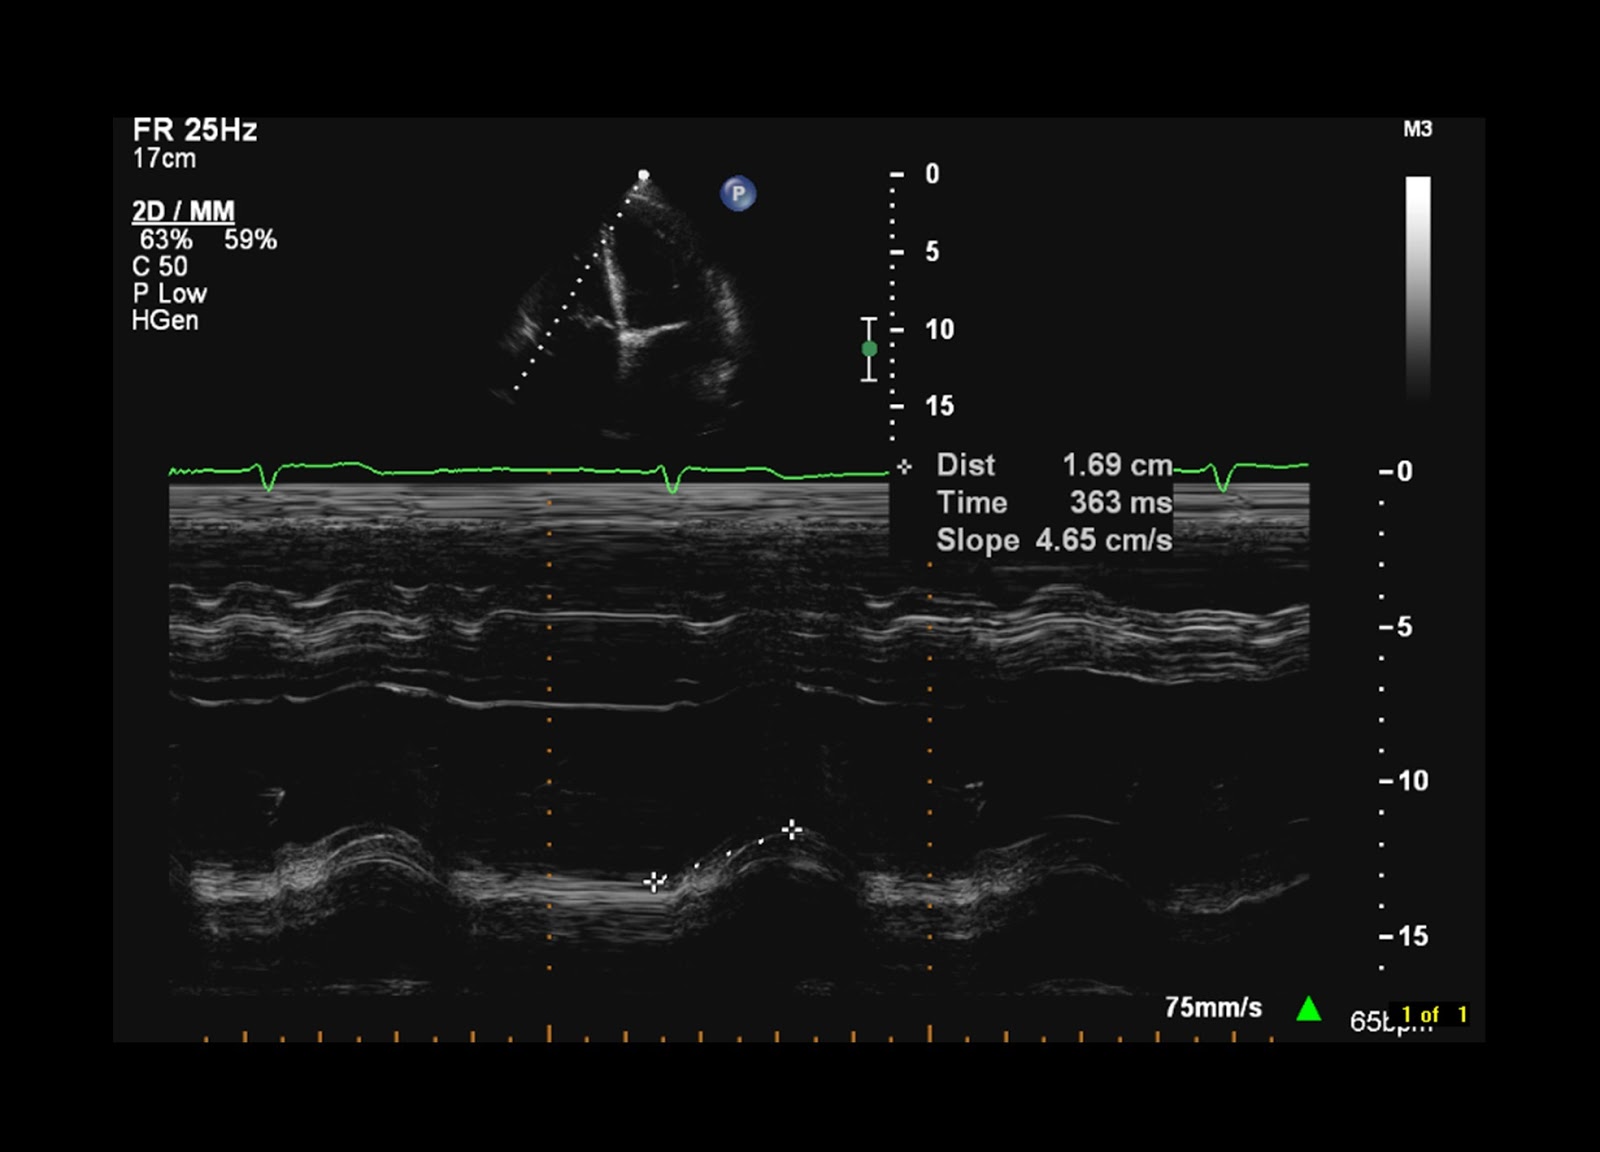

Measurement of TAPSE. In this figure TAPSE = 2.33 cm. TAPSE tricuspid Tapse Normal Range In Cm A tapse < 1.8 cm predicts a stroke volume index <29 ml/m 2 with 87 % accuracy, and. raa ≤22 cm 2 (≤11 cm 2 /m 2) in males, or ≤19 cm 2 (≤11 cm 2 /m 2). All the parameters are accounted for the determination of the normal values of this specified measurement. tapse (tricuspid annular plane. Tapse Normal Range In Cm.

Measurement of tricuspid annular plane systolic excursion (TAPSE) TAPSE Tapse Normal Range In Cm All the parameters are accounted for the determination of the normal values of this specified measurement. tapse (tricuspid annular plane systolic excursion) normal is >1.7cm (less useful post some cardiac surgery). the sensitivity and specificity for the clips in which the measured tapse was <1.5 cm or >1.9 cm was 91.4% (95%. raa ≤22 cm 2 (≤11. Tapse Normal Range In Cm.

Representative echocardiographic images for the measurement of TAPSE. a Tapse Normal Range In Cm All the parameters are accounted for the determination of the normal values of this specified measurement. raa ≤22 cm 2 (≤11 cm 2 /m 2) in males, or ≤19 cm 2 (≤11 cm 2 /m 2). Tapse < 1.6 cm in acute pe is a surrogate for rv strain and may be a sign of submassive pulmonary. in. Tapse Normal Range In Cm.